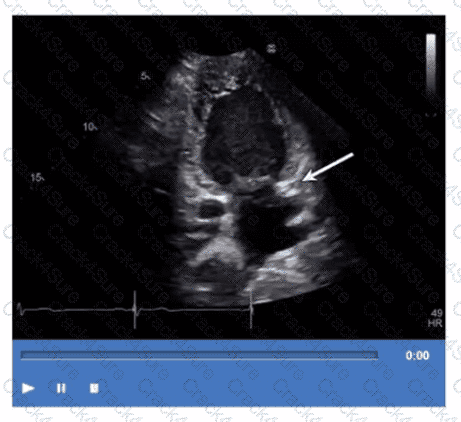

Which structure is the arrow pointing to in this video?

Which finding is demonstrated in this video?